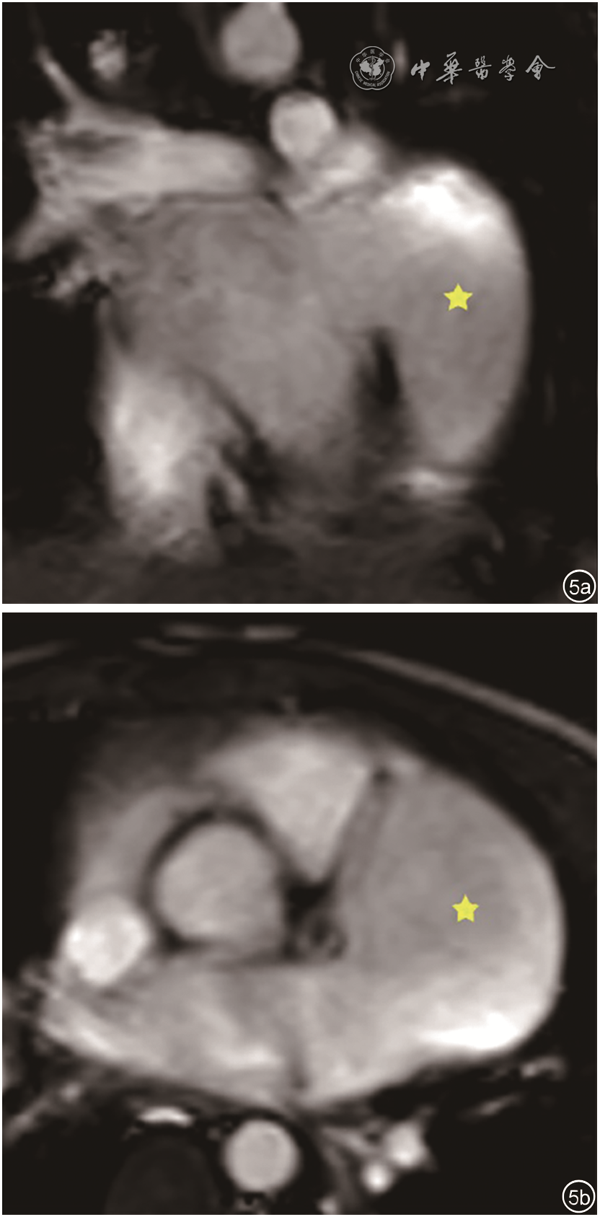

9例患者均经超声心动图检查诊断为LAAA,表现为:(1)四腔心、心底短轴、剑突下等切面二维超声图像可见左心室游离壁外囊状无回声结构,为LAAA;(2)LAAA与左心房交通(图1);(3)彩色多普勒可见LAAA与左心房间血流信号往返(图2);(4)巨大LAAA可压迫左心室或其他毗邻结构(图3);(5)同时可显示合并的其他占位性病变(图4)。

图2 左心耳瘤彩色多普勒超声图像。图示左心耳瘤与左心房交通,其间可见血流信号往返。图a为左心房内血液进入左心耳瘤;图b为左心耳瘤内血液回流入左心房